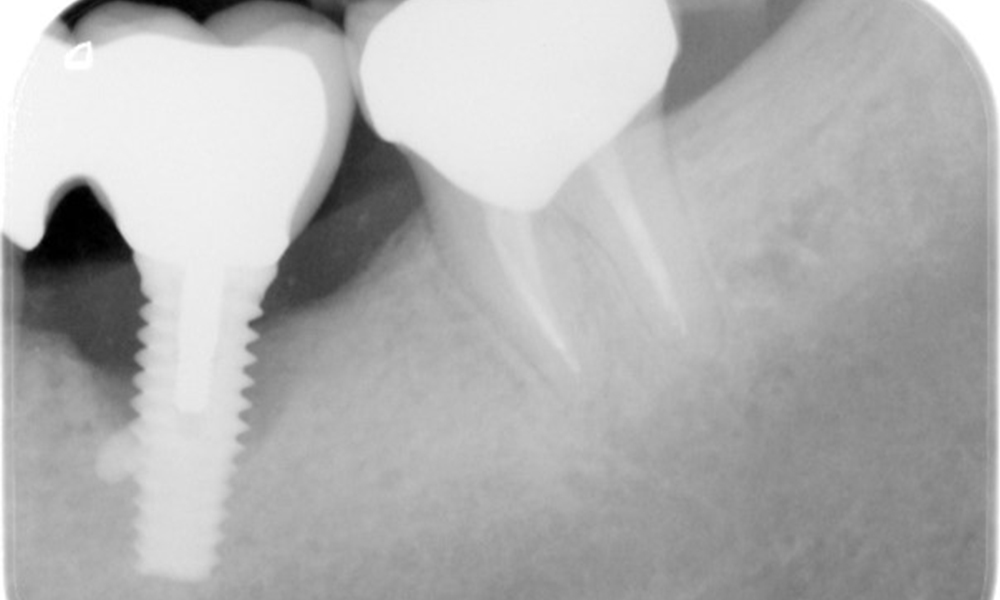

The X-ray images show the progression of bone loss.

The X-ray images show the progression of bone loss. OPG from 29.06.2020 (left) and OPG from 26.02.2024 (right).

The X-ray images show the progression of bone loss in the area of the implant in region 36: dental film from 11.02.2021 (left) and dental film from 18.01.2024 (right).

The patient has no particular risk factors with specific dental implications in his medical history. The key factor, therefore, is the requirement in terms of oral health. In this respect, there is evidence of a probing depth of 5 mm at the implant in the 3rd quadrant and, on the X-ray image, increased bone loss. The patient also has currently stable early periodontal disease and two active initial carious lesions.